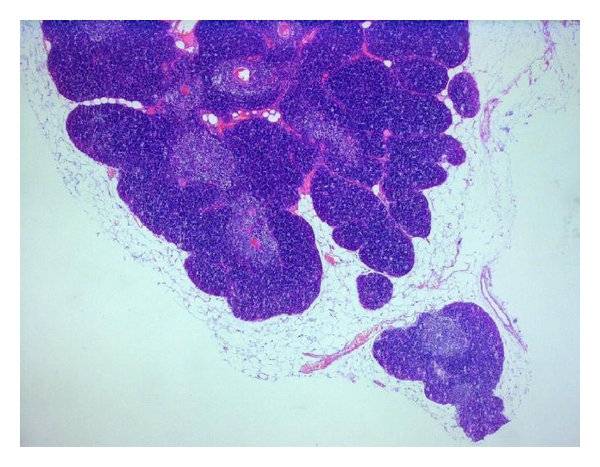

The resected specimens were sent to the Department of Pathology. Gross examination revealed a 11 : 9 : 1 cm-sized grey-coloured, firm, knotty mass weighing 53 g.

The mediastinal mass was essentially composed of histologically normal but increased thymic lobules with preserved corticomedullary differentiation, surrounded by mature fat with hyperaemic vessels enclosed. In the middle of the lobules, several enlarged Hassall corpuscles were observed. Adjacent to the thymic tissue three reactive lymph nodes were found.

Neither histologically nor immunohistochemically (staining with CD3, CD5, CD20, CD79a, p27, cyclin D1, and Ki-67) the suspicion for a posttransplant lymphoproliferative disease or malignancy could be affirmed (Figure 2).